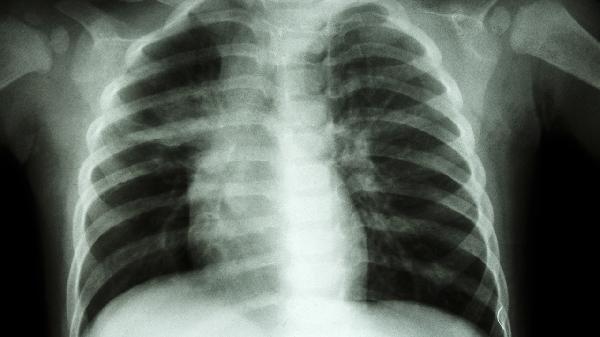

锑尘肺的症状主要有咳嗽、胸闷、胸痛、呼吸困难、乏力等。锑尘肺是由于长期吸入锑及其化合物粉尘引起的职业性肺部疾病,建议患者及时就医治疗。

呼吸困难是锑尘肺进展期的典型表现,初期仅在体力活动时出现,后期静息状态下也可能发生。这与肺组织纤维化导致肺弹性下降、弥散功能障碍有关。患者可能出现气促、呼吸频率增快等症状。需通过氧疗或使用糖皮质激素如醋酸泼尼松片、甲泼尼龙片、地塞米松片等控制病情。

锑尘肺患者应严格避免再次接触锑尘,工作环境需做好防护措施。日常生活中应戒烟,保持室内空气流通,进行适度有氧运动如散步、太极拳等增强肺功能。饮食上多摄入高蛋白、高维生素食物如鱼类、蛋类、新鲜蔬菜水果等。定期复查胸部影像学和肺功能,监测病情变化。如出现症状加重或发热等表现,应及时就医调整治疗方案。